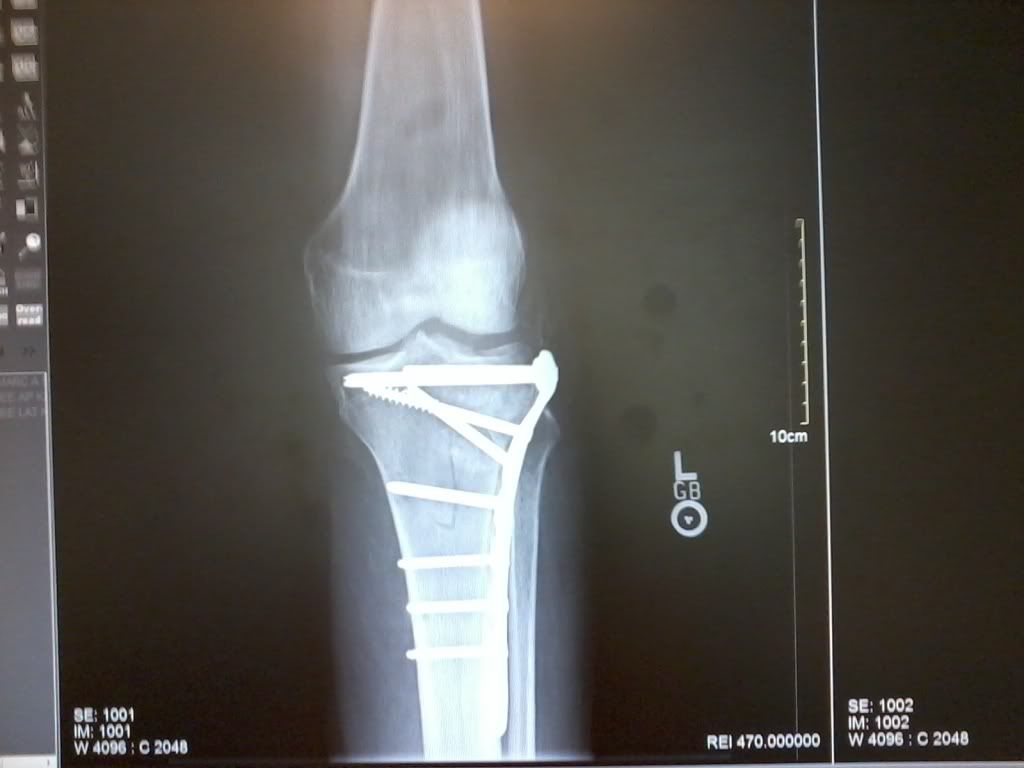

Well, I cannot seem to go to long without tearing something up.  Broke my left knee (Tibia Plateau Compression) and required some repair.  I now have a plate with eight screws and a bone graph holding it together.  The cartilage was damaged but the surgeon said I have a good chance of it being okay for the future.  Riding has been put on hold for another month or so.

Looks like one i may have designed....

Not the pic you posted, that is not what you have in, you have a Prox Tibia Plate, designed to support your tibia and especially that little impacted area.

Listen to your doc and do what they tell you. They should have you into rehab in a day or two...remember, the more you move the sooner you will get back to riding...and do us all a favor...stay the F off the roof!

those screws look like tap-cons

Could be that they were waiting for the swelling to go do and the soft tissues to stablize. Pretty servere fracture. They are correct you will not be running any marathons for a while. Just stick with the Physio and you will be back to riding. They could also be waiting to see how your healing goes, push to hard immediately and your fratre could collapse. So if they are telling to take it slow, do it. Would not want to go and have them re-do it.

Bone quality looks pretty good...best of luck with the healing.  Wink